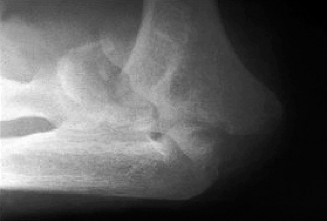

Understand the outcome and prognosis of adhesive capsulitis? CASE 30 Dr. Robert J. Stewart A 44-year-old, right-hand-dominant male with well-controlled diabetes and hypertension presents to clinic with left shoulder pain. The patient denies a history of trauma or injury. He localizes his pain over the superolateral aspect of the shoulder, and it radiates to the deltoid insertion. He has experienced pain over the past few months, but it has progressively become more severe over the past several days. He has difficulty sleeping and with range of motion because of severe pain. While examining the patient, he has a warm and tender left shoulder, and while performing a range of motion evaluation, the patient notes that he has a sensation of “catching.” He has a positive Hawkins sign, negative drop arm test, and pain with a cross body adduction test. A radiograph of the left shoulder is shown in Figure 2–77.

Figure 2–77

Discussion

The correct answer is (D). Calcific tendonitis (CT) is a condition characterized by the buildup of calcium hydroxyapatite crystals within tendons. It typically occurs around synovial joints and has been reported in the hip, paraspinal muscles, hand, and foot. It most frequently occurs around the shoulder in patients who are 30 to 50 years old. No one over the age of 71 has been recorded having this condition. Degenerative calcification and reactive calcification have both been proposed as mechanisms for the deposition of calcium. Although the etiology is not understood, most believe that it is a reactive mechanism involving an active, cell-mediated process in a viable tendon. The cell-mediated process has been divided into three distinct phases: precalcific, calcific, and postcalcific. Depending on the stage, imaging, and physical examination characteristics can differ. The calcific stage can be further classified into three phases: formative, resting, and resorption. Rotator cuff arthropathy is seen in older patients with chronic, massive, rotator cuff tears and glenohumeral osteoarthritis. Septic arthritis can look similar to CT, but this patient has had a history of shoulder pain without fever or other risk factors for infection. Answers C and E are incorrect because there are no signs of osteoarthritis of the AC or GH joint on radiograph or physical examination.

What can be said about the phase of this patient’s shoulder pathology?

The correct answer is (B). In calcific tendonitis (CT), calcium must be deposited for it to be resorbed. Patients presenting during the resorptive phase of the calcific stage will have this type of acute, inflammatory shoulder syndrome that this patient most closely represents. This hyperalgic syndrome will typically last 2 weeks. This is

Which structure is most likely to be affected on the basis of the information obtained thus far, including the radiograph Figure 2–77?

The correct answer is (C). Calcific tendonitis (CT) is most often localized in the supraspinatus tendon. Radiographic views should include a true AP in internal and external rotation, axillary, and scapular-Y to evaluate for calcium deposits in the tendons of the rotator cuff. There are no reports of the deltoid muscle being involved in CT. Radiographs also help to distinguish resorptive and formative phases. Two radiographic types have been described: Type I (associated with the resorptive phase and acute pain) is a deposit that is fluffy or fleecy in appearance with a poorly defined periphery. Type II (associated with the formative phase and chronic pain) has discrete, homogeneous deposits that have a well-defined periphery.